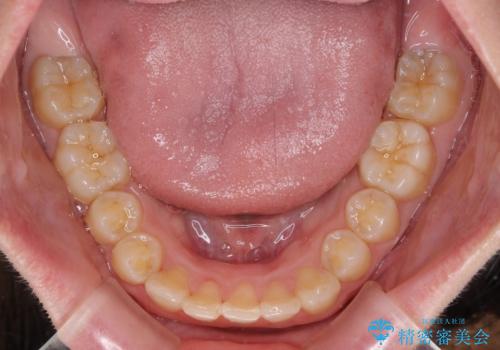

- 八重歯を気にして来院された患者様です。

八重歯の後ろの歯を1歯抜歯し、補助装置(リンガルアーチ)を用いて八重歯の位置を改善し、その後インビザラインにより矯正治療を行うこととしました。

下顎前歯が1本欠損したスリーインサイザーという状態であるため、上下の前歯の咬み込みが深くなったり、奥歯の咬み合わせが理想的なものとならなかったりという仕上がりになってしまいます。

前歯の見た目や奥歯の咬み合わせに、患者様が違和感を感じない状態として治療を終えました。